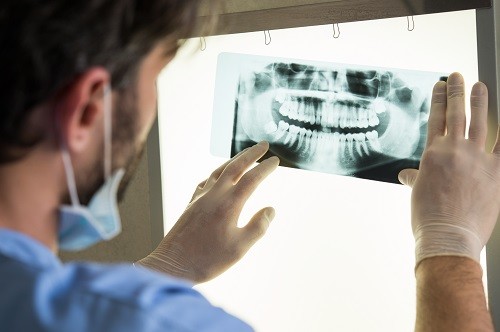

A simple oral exam only allows a dentist to see the visible surfaces of the teeth and the insides of the oral cavity. With the help of an X-ray, dentists can visualize the structures present within the tooth cavity as well as the supporting bone. This allows them to detect and treat dental issues that may otherwise remain undiagnosed and lead to more problems.

Panoramic X-Ray:  This is a type of sizeable dental X-ray that requires a separate machine. The X-ray provides a detailed image of all the teeth in both lower and upper arches, along with the bone and supporting structures. They are usually used for extensive dental work like multiple extractions, braces, dental implants, etc.